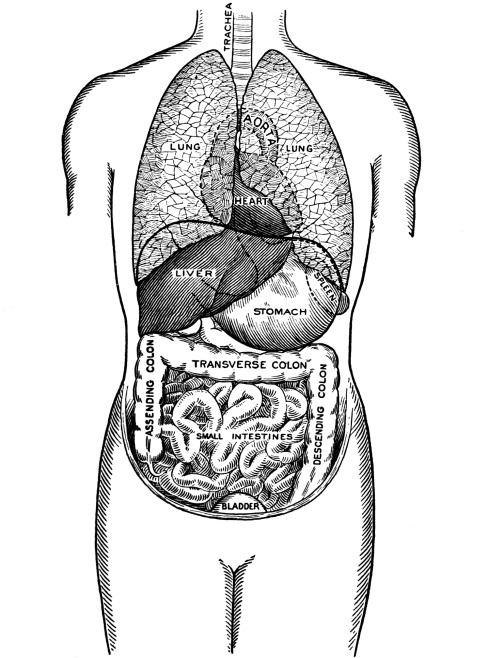

| The Lungs and Respiration | 121 |

The Larynx, 121—The Trachea, 123—The Thyroid Gland, 124—The Thymus Gland, 124—The Bronchi, 125—The Lungs, 125—The Pleura, 125—The Mediastinum, 126—Respiration, 127—Air, 129—Respiratory Sounds, 129—Changes in Air in Lungs, 129—Effect of Respiration on Blood, 130—Nervous Mechanism of Respiration, 130—Variations in Respiration, 131. |

| The Abdomen and the Organs of Digestion and Excretion | 132 |

The Abdominal Cavity, 132—Muscles of the Abdomen, 132—The Peritoneum, 134—Abdominal Regions, 134—Salivary Digestion, 136—The Pharynx, 139—The Esophagus, 138—The Stomach, 138—Gastric Digestion, 139—Vomiting, 140—Intestinal Canal, 141—The Small Intestine, 142—Intestinal Digestion, 143—Absorption in Intestine, 144—The Large Intestine, 145—Food and Metabolism, 147—The Liver, 149—The Gall-bladder, 152—The Pancreas, 153—The Spleen, 153—The Suprarenal Capsules, 154—The Kidneys, 155—The Urine, 156—The Ureters, 159—The Bladder and Urethra, 159. |